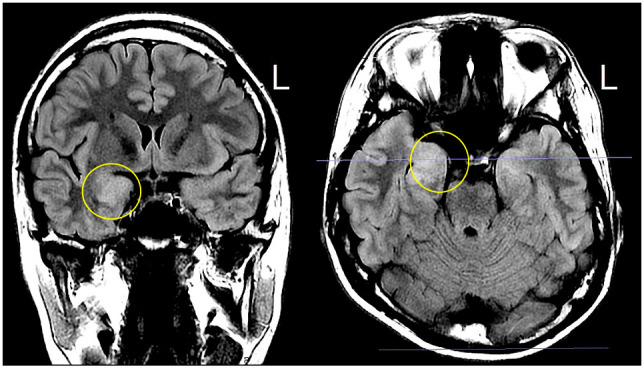

谷氨酸脱羧酶(GAD)是一种催化谷氨酸转化为γ-氨基丁酸(GABA)的酶,GABA是中枢神经系统(CNS)中主要的抑制性神经递质。GAD在中枢神经系统和胰腺β细胞中广泛表达。GAD产生的GABA在胰岛调节胰岛素分泌中起作用。抗广泛性焦虑症抗体是1型糖尿病(T1DM)的标志物,也与僵硬人综合征(SPS)和其他几种神经系统疾病有关,包括共济失调、认知障碍、边缘脑炎和癫痫,统称为广泛性焦虑症抗体谱障碍(GAD- sd)。我们报告一例17岁男性患者在异基因造血细胞移植(HCT)后出现GAD-SD和T1DM。他表现出记忆障碍,包括眩晕感,伴有呕吐和头痛,并表现出异常的脑磁共振成像和脑电图结果。除了空腹血糖和糖化血红蛋白水平升高外,血清和脑脊液中检测到抗广泛性ad抗体水平明显升高。根据这些发现,患者被诊断为GAD-SD和T1DM,并接受甲基强的松龙治疗,随后每日多次注射胰岛素。我们还回顾了先前报道的HCT和多个胰岛相关抗体阳性的GAD-SD病例。

Glutamic acid decarboxylase (GAD) is an enzyme that catalyzes the conversion of glutamic acid into γ-aminobutyric acid (GABA), the primary inhibitory neurotransmitter in the central nervous system (CNS). GAD is widely expressed in the CNS and pancreatic β-cells. GABA produced by GAD plays a role in regulating insulin secretion in pancreatic islets. Anti-GAD antibody is an established marker of type 1 diabetes mellitus (T1DM) and is also associated with stiff-person syndrome (SPS) and several other neurological disorders, including ataxia, cognitive impairment, limbic encephalitis, and epilepsy, collectively referred to as GAD antibody-spectrum disorders (GAD-SD). We report the case of a 17-year-old male patient who developed GAD-SD and T1DM after allogeneic hematopoietic cell transplantation (HCT). He presented with memory disorders, including feelings of déjà vu, accompanied by vomiting and headaches, and exhibited abnormal brain magnetic resonance imaging and electroencephalogram results. In addition to elevated fasting plasma glucose and glycated hemoglobin levels, markedly elevated anti-GAD antibody levels were detected in the serum and cerebrospinal fluid. Based on these findings, the patient was diagnosed with GAD-SD and T1DM and treated with methylprednisolone, followed by multiple daily insulin injections. We also reviewed previously reported cases of GAD-SD following HCT and multiple positive islet-related antibodies.